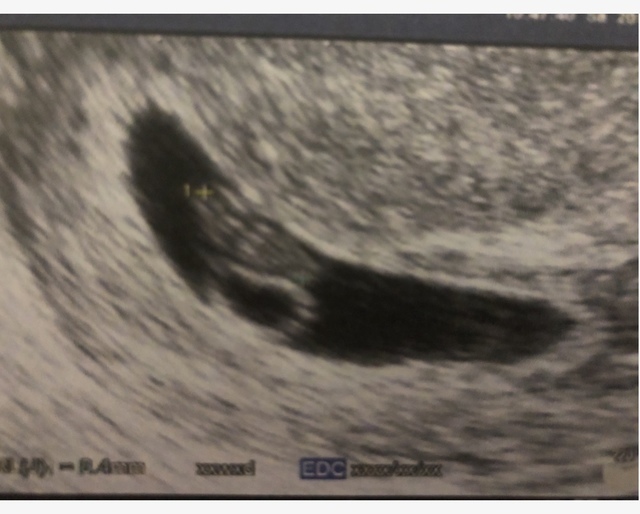

7週6日(7w6d・性別不明)|しのたそ さん(27歳)

エコー写真撮影時のエピソード:

2回目の妊娠。前回が残念な結果だったので授かれたうれしさと今回は大丈夫かなという不安がありました。きちんと安定してきてからみんなに報告しようと思いました。

主人は子どもが好きでお腹によく声をかけたり、胎教にいい曲を流したりしてくれました。